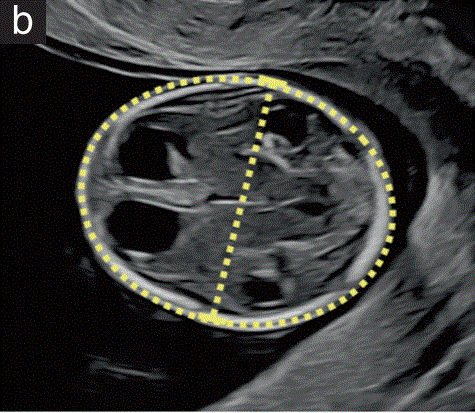

双顶径(BPD)和头围是指 胎儿头部的最大对称轴位测量(图1-b)

已经描述了两种测量BPD的技术,将卡尺从外到内(前缘)或从外到外,垂直于中线镰。应根据用于建立诺模图的方法进行测量。

根据CRL和/或腹围(AC)或腹横径调整BPD测量值(TAD)可能有助于早期筛查脊髓脊膜膨出和前脑无裂畸形。

图1 11+0至14+0周胎儿超声检查可获得的测量值。(b) 丘脑水平的胎儿头部横断切面,显示双顶径(BPD)的测量值,卡尺从外到外放置,和头围。在这个平面上可以看到中线大脑镰和丘脑。在一些国家指南中,BPD测量是通过测量外径到内径来实现的。